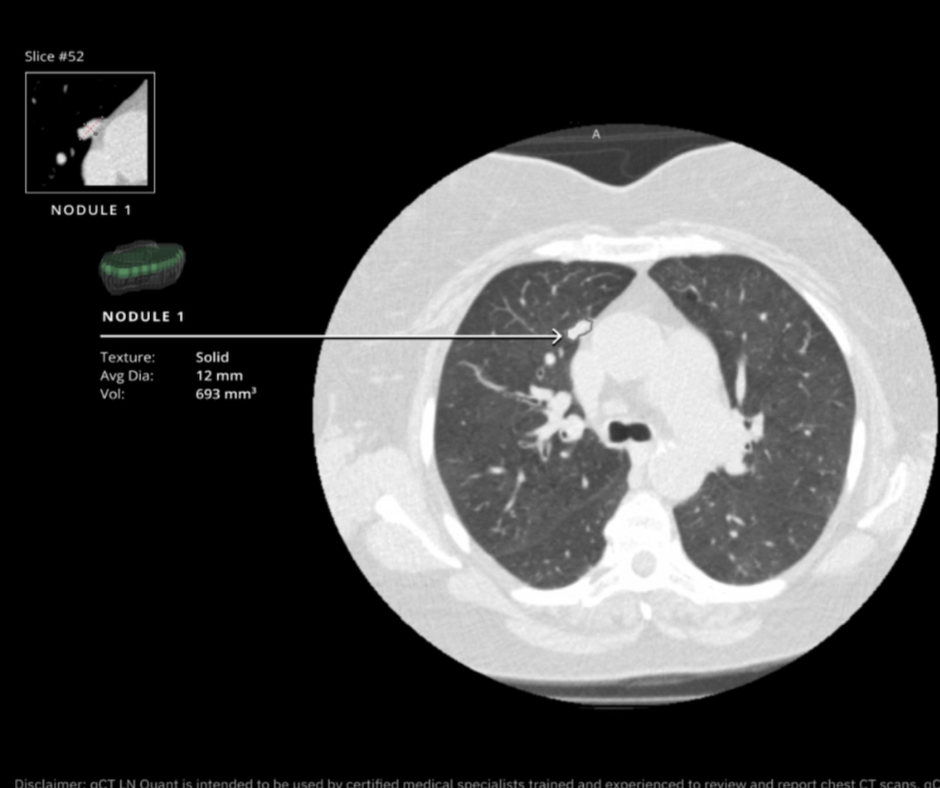

The AI-powered qCT LN Quant software reportedly generates 2D and 3D reconstructions and facilitates assessment of morphologic data across multiple thoracic studies.

In addition to providing short-axis, long-axis and average diameter measurements of lung nodules, the qCT LN Quant software enables radiologists to determine estimated volume doubling time and assess nodule tracking for multiple thoracic studies, according to Qure.ai, the developer of qCT LN Quant.

The company also points out that qCT LN Quant provides Brock malignancy risk scoring, 2D and 3D image reconstructions and management suggestions based on Fleischner Society guidelines.